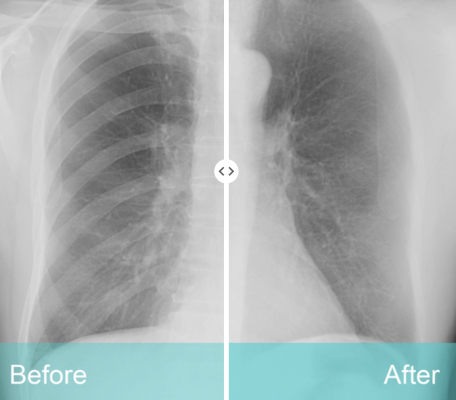

While traditional X-rays help identify lung abnormalities, the body’s 12 sets of ribs and clavicles stand in the way of a clear view. Radiologists are often at the mercy of what their eyes can see. ClearRead’s unique suppression technology removes obstructions from an image, allowing the radiologist to detect actionable nodules more effectively on frontal chest X-rays.

ClearRead X-ray bone suppression helps radiologists detect 1 out of 6 previously missed nodules on an image (17% improved nodule detection)1, and it significantly improves fungal infection detection2.